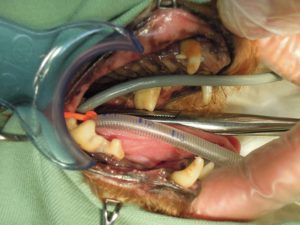

6.歯周病のため右側上顎の歯を全て抜歯し、

7.右側下顎の歯も骨折に注意して抜歯し、

8.左側上顎の歯も全て抜歯し、

9.左側下顎も全て抜歯しました。

顎先が細くやせた状態になっています。